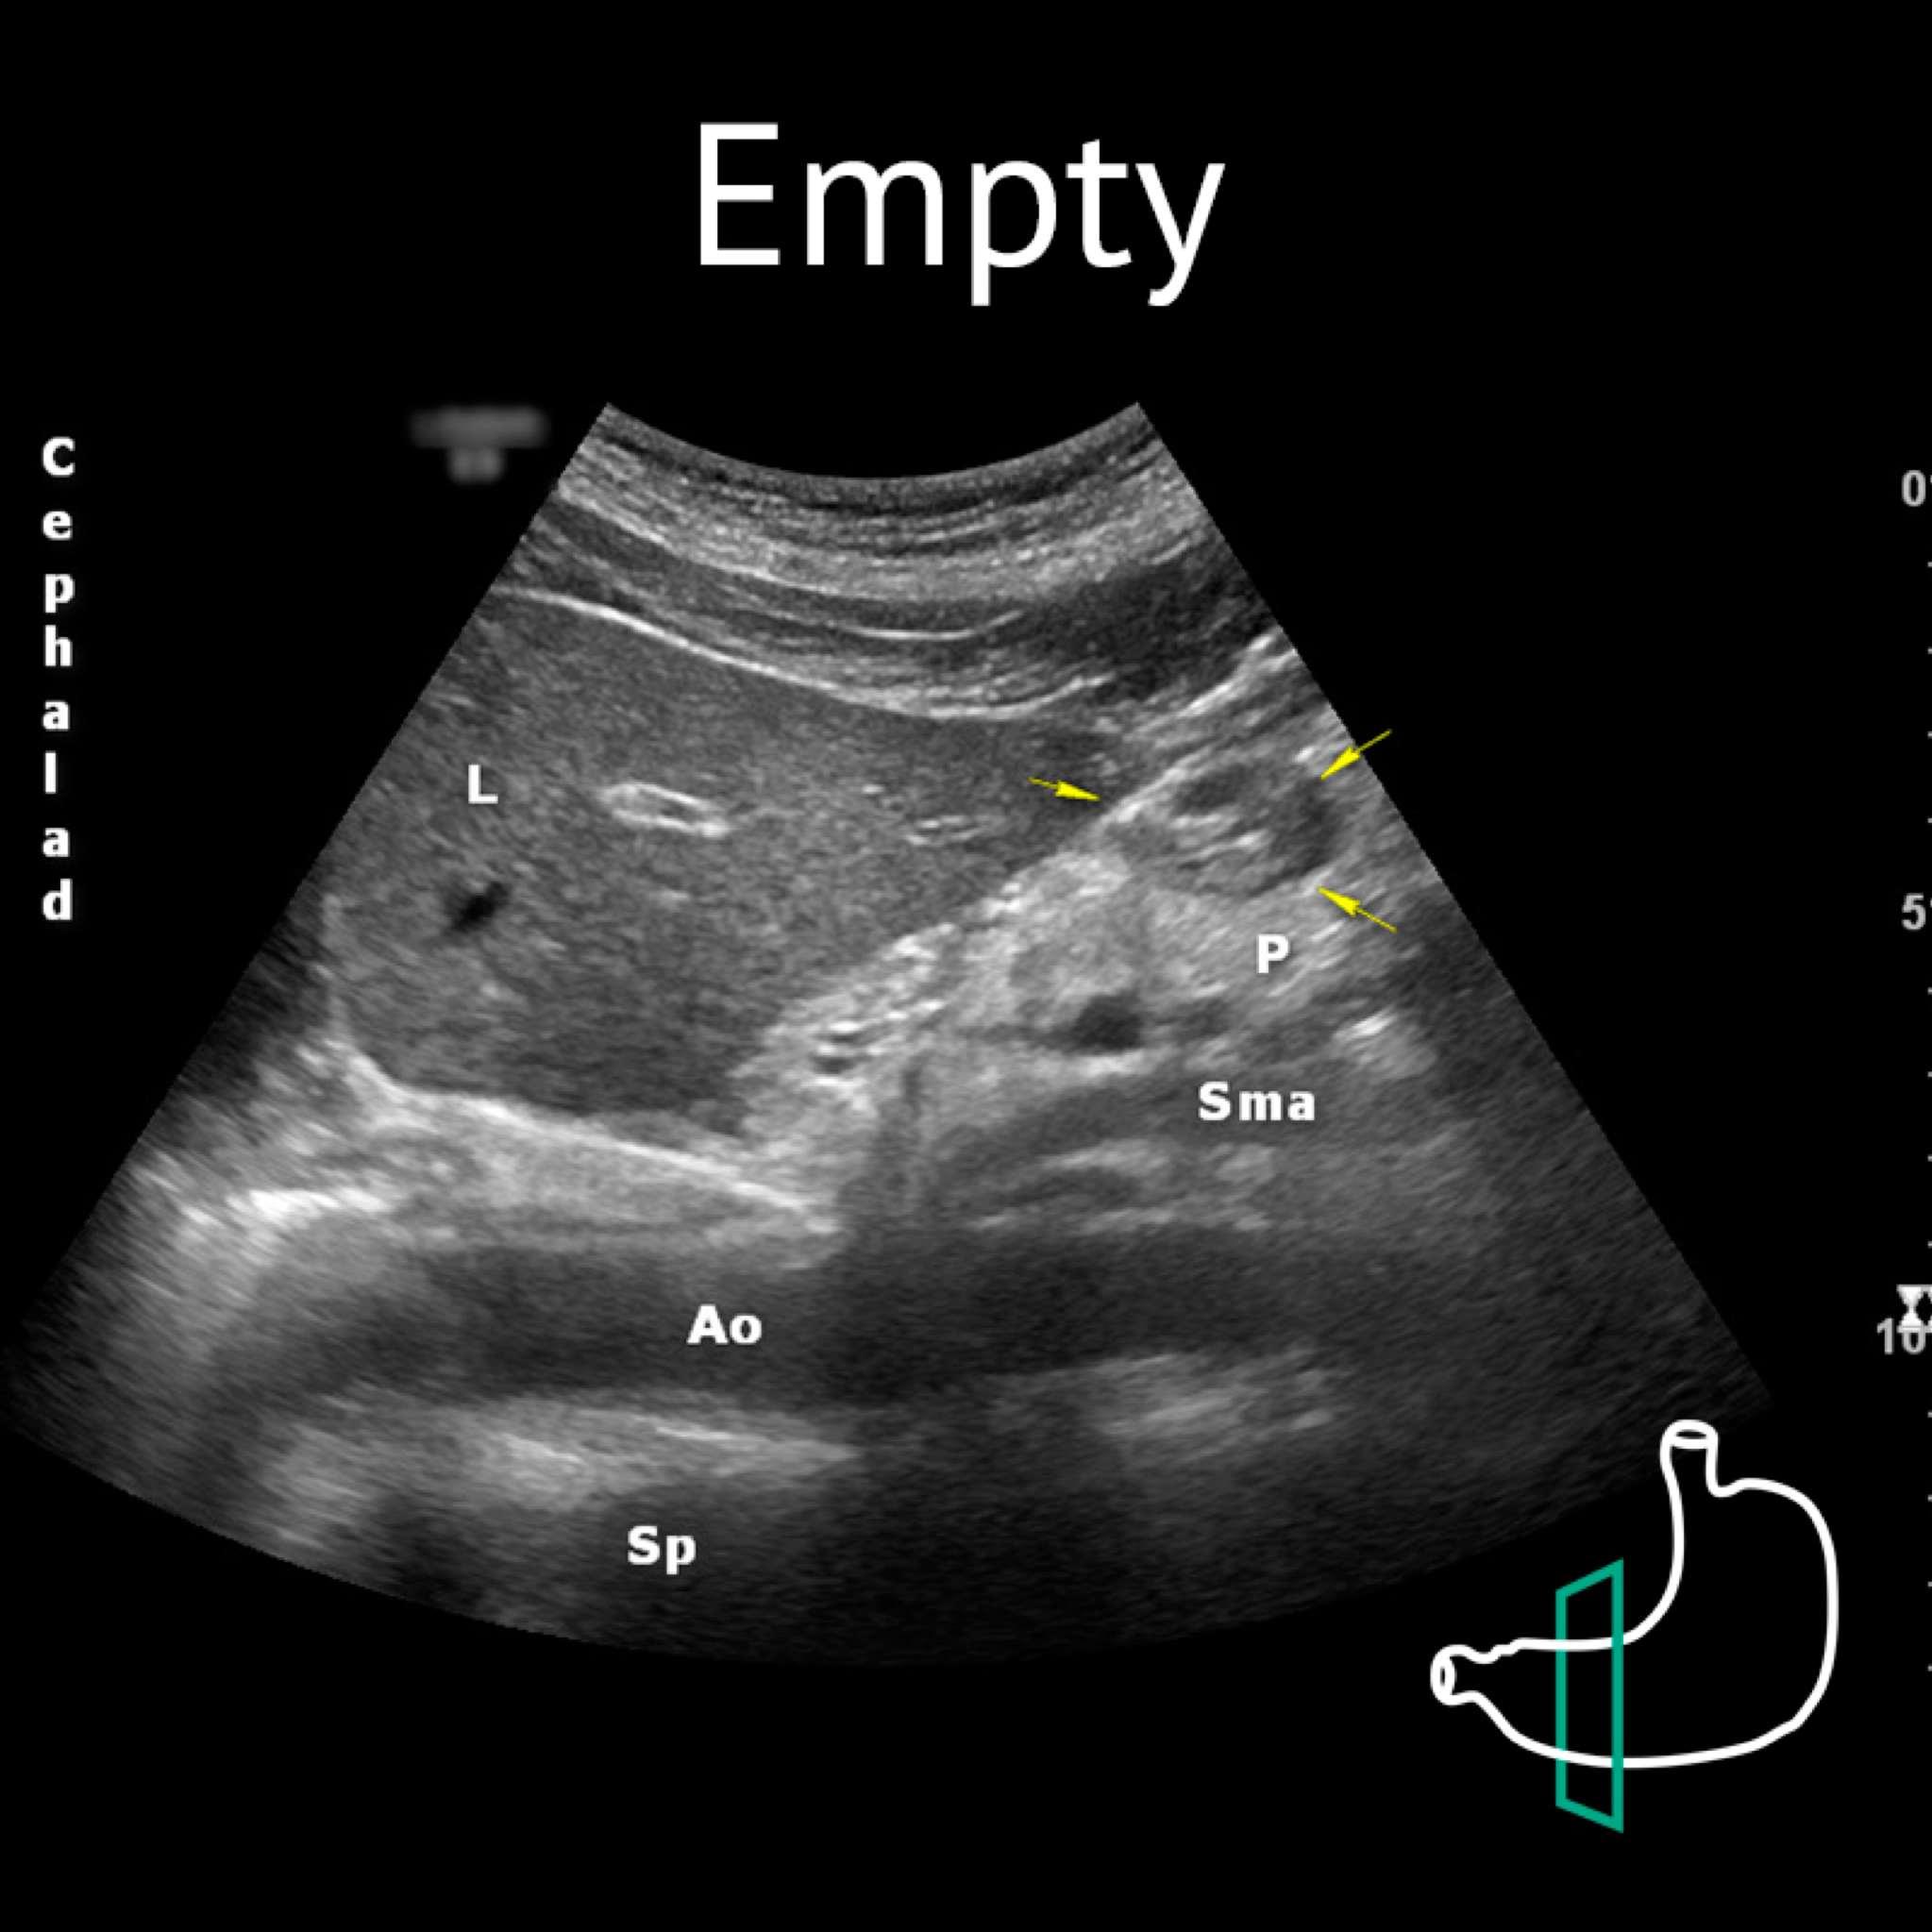

Ao: aorta; L: liver; P: pancreas; Sma: superior mesenteric artery; Sp: spine Yellow arrows: antrum